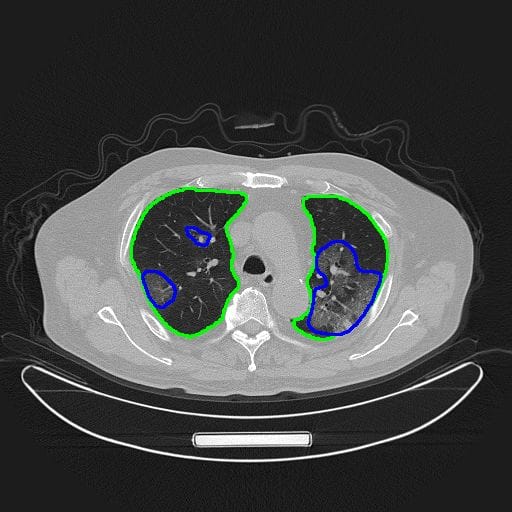

L’un des exemples, c’est autour du scanner thoracique qui peut détecter des changements pathologiques des poumons, les médecins d’imagerie assument une lourde charge de travail, car non seulement la détection des cas suspects nécessite un examen tomodensitométrique, mais les patients sous traitement doivent également subir un scanner tous les cinq jours en moyenne.

Un scanner thoracique génère généralement environ 300 images, ce qui prend cinq à quinze minutes aux médecins pour les examiner à l’œil nu, mais la plate-forme d’imagerie et de diagnostic Tencent AMIS IA peut fournir aux médecins une référence diagnostique en une minute seulement, améliorant considérablement l’efficacité du diagnostic et fournissant un traitement rapide aux patients. La technologie IA effectue une segmentation automatique des images : les boucles vertes et bleues ci-dessous indiquent respectivement les lésions pulmonaires et Covid-19.